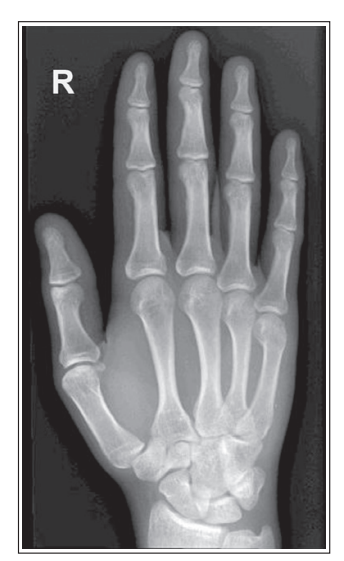

5th metacarpal is in profile

Slight external rotation